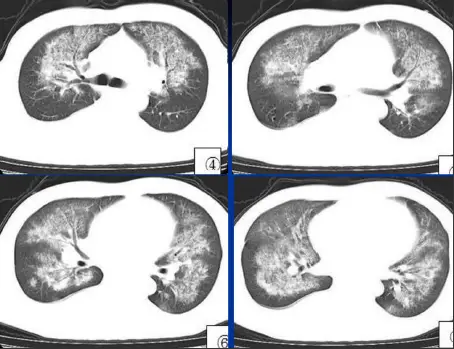

病例:男,44岁,咳嗽,咳血一周。3天前双侧膝关节疼痛,按风湿输水治疗时突然胸闷、气短。化验肾功能衰竭。高血压病3年。

肾性肺水肿,主要是水钠潴留过多、贫血(肾衰导致促红细胞生成素降低)致血浆胶体渗透压降低,临床症状主要表现为少尿、高血压及心力衰竭。肾性肺水肿肺纹理普遍增粗,血管蒂增宽。肺实变阴影中央分布较多。

①血液密度减低;

②肺泡性肺水肿及间质性肺水同时存在,而以肺泡性肺水肿为主;

③胸腔积液。又称尿毒症肺。

肾性肺水肿最终以心力衰竭的病理生理变化表现出来,通过病史临床表现及肾功能检查等,可作肾性肺水肿诊断。